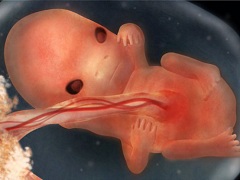

На 9 неделе беременности плацента полностью взяла на себя задачу жизнеобеспечения плода, а будущий ребенок продолжает расти и развиваться. Размер плода на 9 неделе беременности составляет до 30 мм в длину, вес до 2 г. Внешний вид его все больше принимает человеческие черты – характерно удлинилось тело, хвост превратился в копчик, голова приобрела округлую форму и имеет выраженный наклон вперед, можно различить шею. Кожа плода очень тонкая и полупрозрачная, через нее видны сосуды.

На УЗИ в 9 недель беременности можно заметить, что руки и ноги плода остаются непропорционально короткими, со сформированными уже пальчиками, на руках начинают закладываться ногти. Изменения затрагивают и лицо – глаза закрыты веками, широко расставлены, формируется ротовая щель. Ушные раковины на 9 неделе беременности уже хорошо различимы, но внутреннее ухо недоразвито, и плод еще не слышит.

В головном мозге на 9 неделе беременности идет интенсивное развитие мозжечка – отдела, отвечающего за равновесие и координацию тела в пространстве. Закладывается гипофиз – отдел мозга, который отвечает за регуляцию различных процессов жизнедеятельности организма и вырабатывает некоторые гормоны. В это же время формируются спинномозговые, черепные и межпозвоночные нервы. Также в надпочечниках выделяется слой клеток, отвечающих за образование гормона адреналина.

В 9 недель беременности происходит закладка лимфатических узлов, грудных желез, яички у будущих мальчиков начинают опускаться из брюшной полости в мошонку.